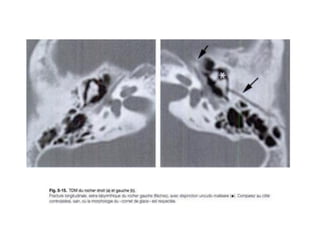

FRACTURE DE LA BASE DU CRANE

En général, il s’agit de :

• Fracture du sphénoïde généralement linéaire et grave

secondaire à un traumatisme violent

• Fracture de la voûte irradiée à la base

• Fracture généralement ouverte (donc surinfections)

• Fractures des orbites, des sinus et surtout des rochers

Intérêt majeur de la T.D.M pour un bilan lésionnel

FRACTURE DE LABASE DU CRANE En général, il s’agit de : • Fracture du sphénoïde généralement linéaire et grave secondaire à un traumatisme violent • Fracture de la voûte irradiée à la base • Fracture généralement ouverte (donc surinfections) • Fractures des orbites, des sinus et surtout des rochers Intérêt majeur de la T.D.M pour un bilan lésionnel RECHERCHER TOUJOURS DES LESIONS SOUS JACENTES ASSOCIEES → HED, ATTEINTE PARENCHYMATEUSE ET MENINGEE